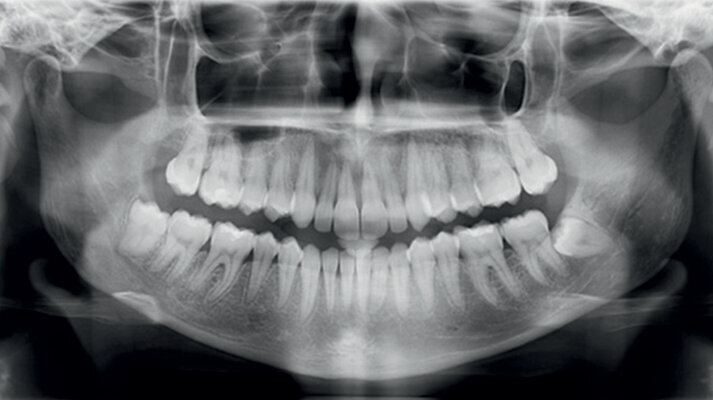

25letá pacientka požadovala estetickou ortodontickou léčbu, kterou nebylo jednoduché naplánovat vzhledem k tomu, že je umělkyní a cestuje po celé Evropě. Během vyšetření byla diagnostikována II. třída 1. oddělení, mírné stěsnání v dolní čelisti a středně těžké stěsnání v čelisti horní. Incizální schůdek byl 10 mm. Profilová zkouška jasně ukazuje protruzní postavení rtů (obr. 1a–c). Pacientka odmítla extrakční nebo ortodonticko-chirurgickou léčbu. Vhledem k jejím požadavkům na estetiku byl léčebný plán stanoven takto: léčba fóliovými aparáty Invisalign (Align Technology) s výsledným postavením molárů i špičáků v I. třídě, které bude dosaženo postupnou distalizací horních molárů s pomocí kompozitních attachmentů na všech distalizovaných zubech a tahů II. třídy (obr. 2, 3). Pacientce bylo doporučeno nosit fólie a tahy II. třídy nejméně 21 hodin denně. Dále pacientka používala přístroj AcceleDent 20 minut denně po celou dobu trvání ortodontické léčby. Fólie byly měněny každé 2 týdny, dokud nebyly druhé horní moláry plně distalizovány, potom každých 10 dnů, dokud nebyly první moláry ve své finální pozici, a nakonec každých sedm dní až do konce léčby.

ClinCheck (Align Technology) software navrhl k získání požadovaných výsledků 63 alignerů s předepsaným množstvím atachmentů a nasazením tahů II. třídy. Odhadovaná doba léčby byla přibližně 30 měsíců. Nicméně protože se pacientka rozhodla používat přístroj AcceleDent, léčba byla ukončena již po 18 měsících bez nutnosti refinementu, tedy s původně plánovanými 63 alignery (obr. 4a–c, 5a–c).

Klinický výsledek byl vynikající, postavení molárů i špičáků v I. třídě, vyhovující překus a předkus. I profil dolní třetiny obličeje byl výrazně lepší.

Na překrytí kefalometrických snímků je zřejmá distalizace molárů o 6 mm bez výraznějšího sklonu a s ideálním bukolingválním sklonem řezáků. Tahy druhé třídy umožnily protrakci mandibuly o 1,5 mm. Jako retenční aparáty jsme zvolili Vivera retainery (Align Technology) (obr. 6, 7a–c, 8a–c).